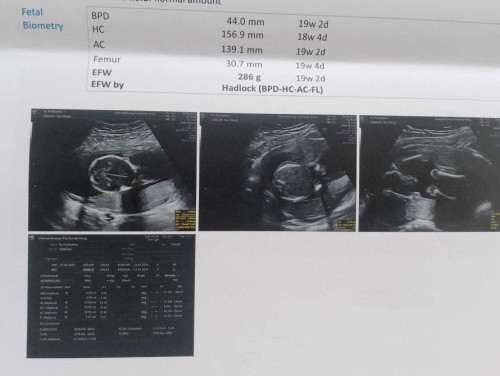

อายุครรภ์ตอนนี้19w2d แต่วัดเส้นรอบวงศีรษะ ทารกในครรภ์ได้น้อยกว่าอายุครรภ์แบบนี้จะเป็นไรไหมคะ#ขอบคุณล่วงหน้านะคะ

มันเป็นการคาดเดาของเครื่องซาวด์ค่ะ ถ้าหมอไม่ได้บอกอะไรก็คือปกติค่ะ แต่ละส่วนอายุครรภ์จะไม่ตรงกันค่ะแม่

บวกลบ 10 วันไม่ห่างกันมาก ถือว่าตามอายุครรภ์ค่ะ